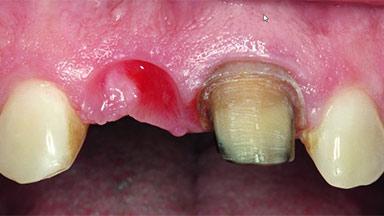

A healthy 38-year-old male patient was referred for replacement of a failing tooth-supported cantilever fixed dental prosthesis on teeth 11 and 21. The patient reported a history of trauma at 13 years of age that had resulted in the subsequent loss of tooth 11, as well as endodontic treatment of the adjacent abutment tooth 21. A metal-ceramic cantilever fixed dental prosthesis replacing tooth 11 had been provided by his general dentist several years after the loss of the tooth, with tooth 21 as the sole abutment. At the time of initial presentation, this restoration had been in service for over 20 years.